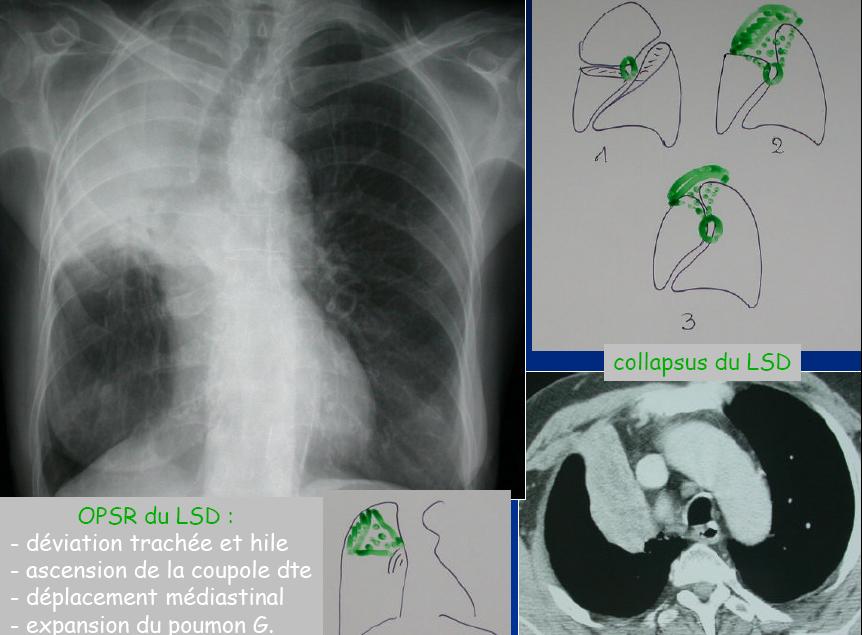

Directs : opacité pulmonaire systématisée rétractile et déplacement des scissures

Indirects : Elévation de la coupole diaphragmatique

Déplacement des structures médiastinales et du hile du côté du collapsus

Hyperaération compensatrice des autre lobes (bilatéraux)